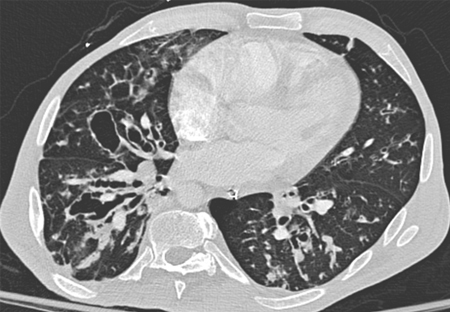

What would you see on a CXR/CT of bronchiectasis?

CXR - obscured hemidiaphragm, thin-walled ring shadows with or without fluid levels, tram lines (sign of thickened tapered walls of bronchiectasis), tubular or ovoid opacities

CT - thickened, dilated airways with or without air fluid levels; varicose constrictions along airways; cysts and/or tree-in-bud pattern